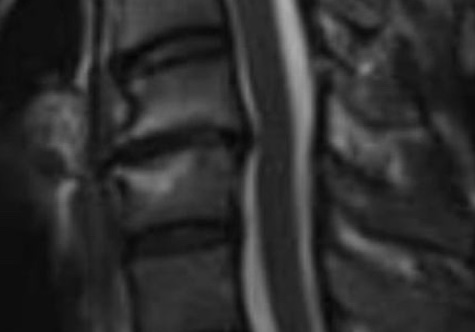

これらの中でも脊柱管狭窄症は、整形外科的にも難治な疾患だといえるでしょう。当院では、脊柱管狭窄症に、最新の低出力レーザー(痛みはありません)と鍼を融合した治療を行ない、成果を上げています。写真は、私の頚部MRI画像ですが、脊椎が脊髄を後ろ向けに押し込んでいます。数ヶ月に及び首肩腕指先までも、強烈な痛みと痺れでまさに地獄でした。病院で手術を願い出ましたが、場所が危険なために医師は行いたくないようでした。そこで鍼灸とレーザーを始めて3、4ヶ月で完治。10年以上経っても再発の兆しはありません。通常の治療で芳しくない方は、お気軽にご相談ください。

当院での治療 従来の鍼灸治療に加えて、脊柱管内、脊髄に十分に行き渡るように、範囲を拡大した光線を照射します。上記のように、私の頚部もこれで完治しました。